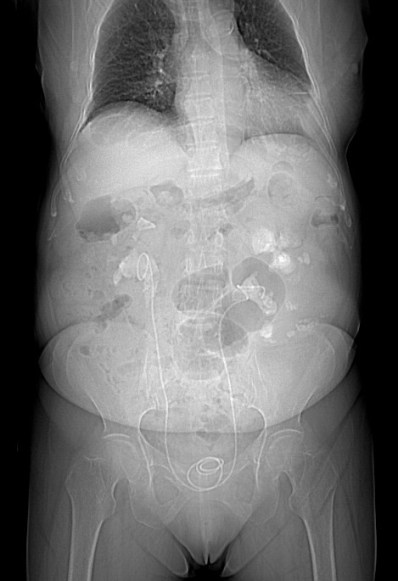

Radiografía:

Es limitada. Antes de la introducción del CT multidetector, se realizaba el diagnóstico a traves de los siguientes hallazgos:

- Cálculo coraliforme: no está siempre presente y no es específico de esta patología.

- Agrandamiento de la silueta renal

- Borramiento del psoas ipsilateral.

- Si se realiza urografía intravenosa: función renal disminuida, hidronefrosis, defectos de repleción por litiasis.

Paciente mujer de 62 años que acude por decaimiento general con fiebre y dolor en flanco izquierdo. Ingresa en UVI por signos de sepsis

Nos cuenta antecedentes de pielonefritis e hidronefrosis crónica.

Hallazgos en imagen:

Estos hallazgos pueden ser dificiles de interpretar, ya que una paciente con hidronefrosis crónica y litiasis en el uréter puede haber sufrido una obstrucción que origina un cuadro de dolor en FRI con ruptura de cálices y colección extra axial. Otra probabilidad puede ser un angiomiolipoma que ha roto un aneurisma y ha producido un sangrado. También podríamos estar ante una pionefrosis aunque dada dada la clínica, los antecedentes y al observar los hallazgos en TC podríamos establecer la sospecha de pielonefritis xantunogranulomatosa con alta probabilidad. La confrimación vendrá dada con la nefrostomía y estudio de anatomía patológica.